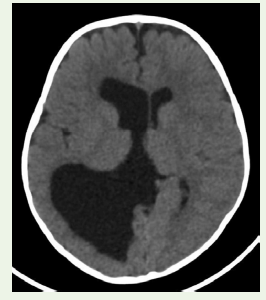

Case 5: A 1-year-old girl with new-onset seizures had isolated enlargement of the right lateral ventricle on CT (Figure 5), consistent with unilateral hydrocephalus. In each patient, imaging 昀椀ndings guided targeted management (medical therapy and, when indicated, surgical intervention).

Figure 5: Axial CT image showing marked dilation of the right lateral

ventricle with thinning of the adjacent right cerebral hemisphere and midline

shift to the left, consistent with unilateral hydrocephalus due to foramen of

Imaging findings: Cranial CT showed marked enlargement of

temporal lobe and effacement of cortical sulci (Figure5).

The enlarged ventricle caused a midline shi (~8 mm) to the le. No mass lesion or hemorrhage was seen. These findings indicate significant unilateral right-sided hydrocephalus.

Diagnosis: Imaging confirmed an isolated dilation of the right

lateral ventricle, most likely due to congenital stenosis of the right

foramen of Monro (given the absence of a tumor or hemorrhage).

Management: The patient was treated with antiepileptic

medication and underwent right ventriculoperitoneal shunt

placement to relieve the hydrocephalus.